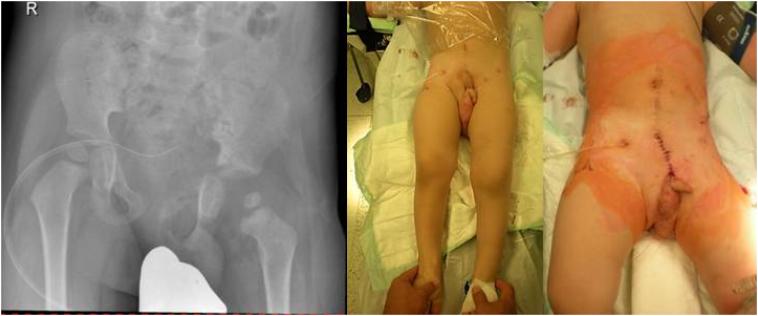

We report on a 14 months old toddler who sustained a traumatic hemipelvectomy by being crushed between a car and a stone wall. After stabilization in the resuscitation room he was treated operatively by laparotomy, osteosynthesis of the pelvic ring, reconstruction of the both external iliac vessels and the urethra and reposition of the testicles. After 66 days he was discharged into rehabilitation. Implants were removed after eight months. 20 months after the injury, the leg was plegic, initial radiological signs of femoral head necrosis showed up but the infant was able to walk with an orthesis and a walker. Up to our knowledge, this is the youngest patient described in the literature with a survived traumatic hemipelvectomy and salvaged limb.